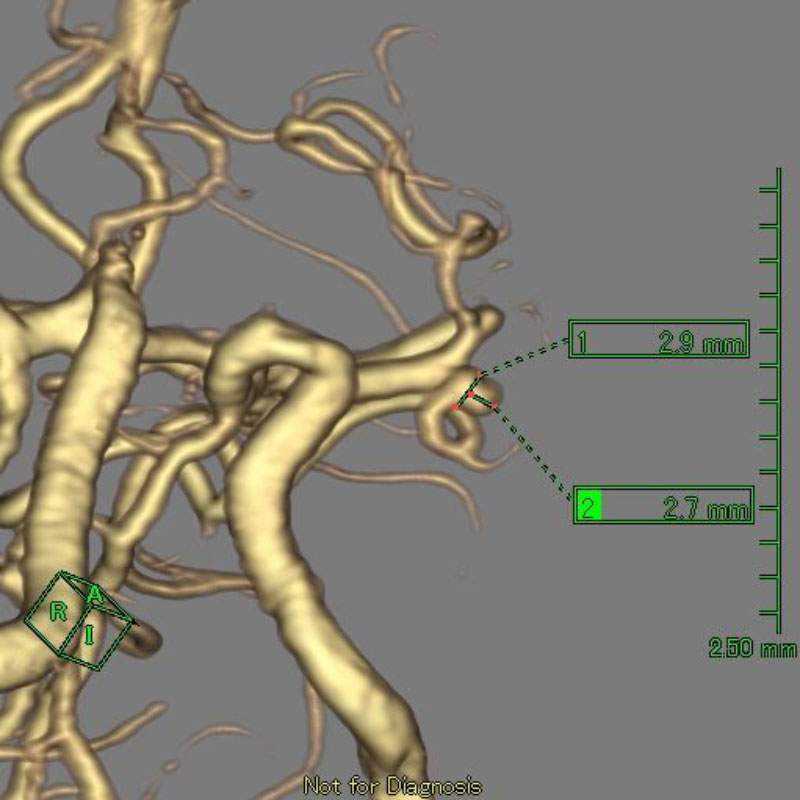

1

'26年1月

40代

右中大脳動脈瘤

クリッピング術

手術前

クリップ前

クリップ後

術後血管撮影